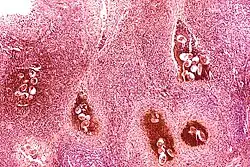

Certain bacterial infections also increase the risk of cancer, as seen in Helicobacter pylori-induced gastric carcinoma.[79] The mechanism by which H. pylori causes cancer may involve chronic inflammation or the direct action of some of the bacteria's virulence factors.[80] Parasitic infections strongly associated with cancer include Schistosoma haematobium (squamous cell carcinoma of the bladder) and the liver flukes, Opisthorchis viverrini and Clonorchis sinensis (cholangiocarcinoma).[81] Inflammation triggered by the worm's eggs appears to be the cancer-causing mechanism. Certain parasitic infections can also increase the presence of carcinogenic compounds in the body, leading to the development of cancers.[82] Tuberculosis infection, caused by the mycobacterium M. tuberculosis, has also been linked with the development of lung cancer.[83]

Inflammation